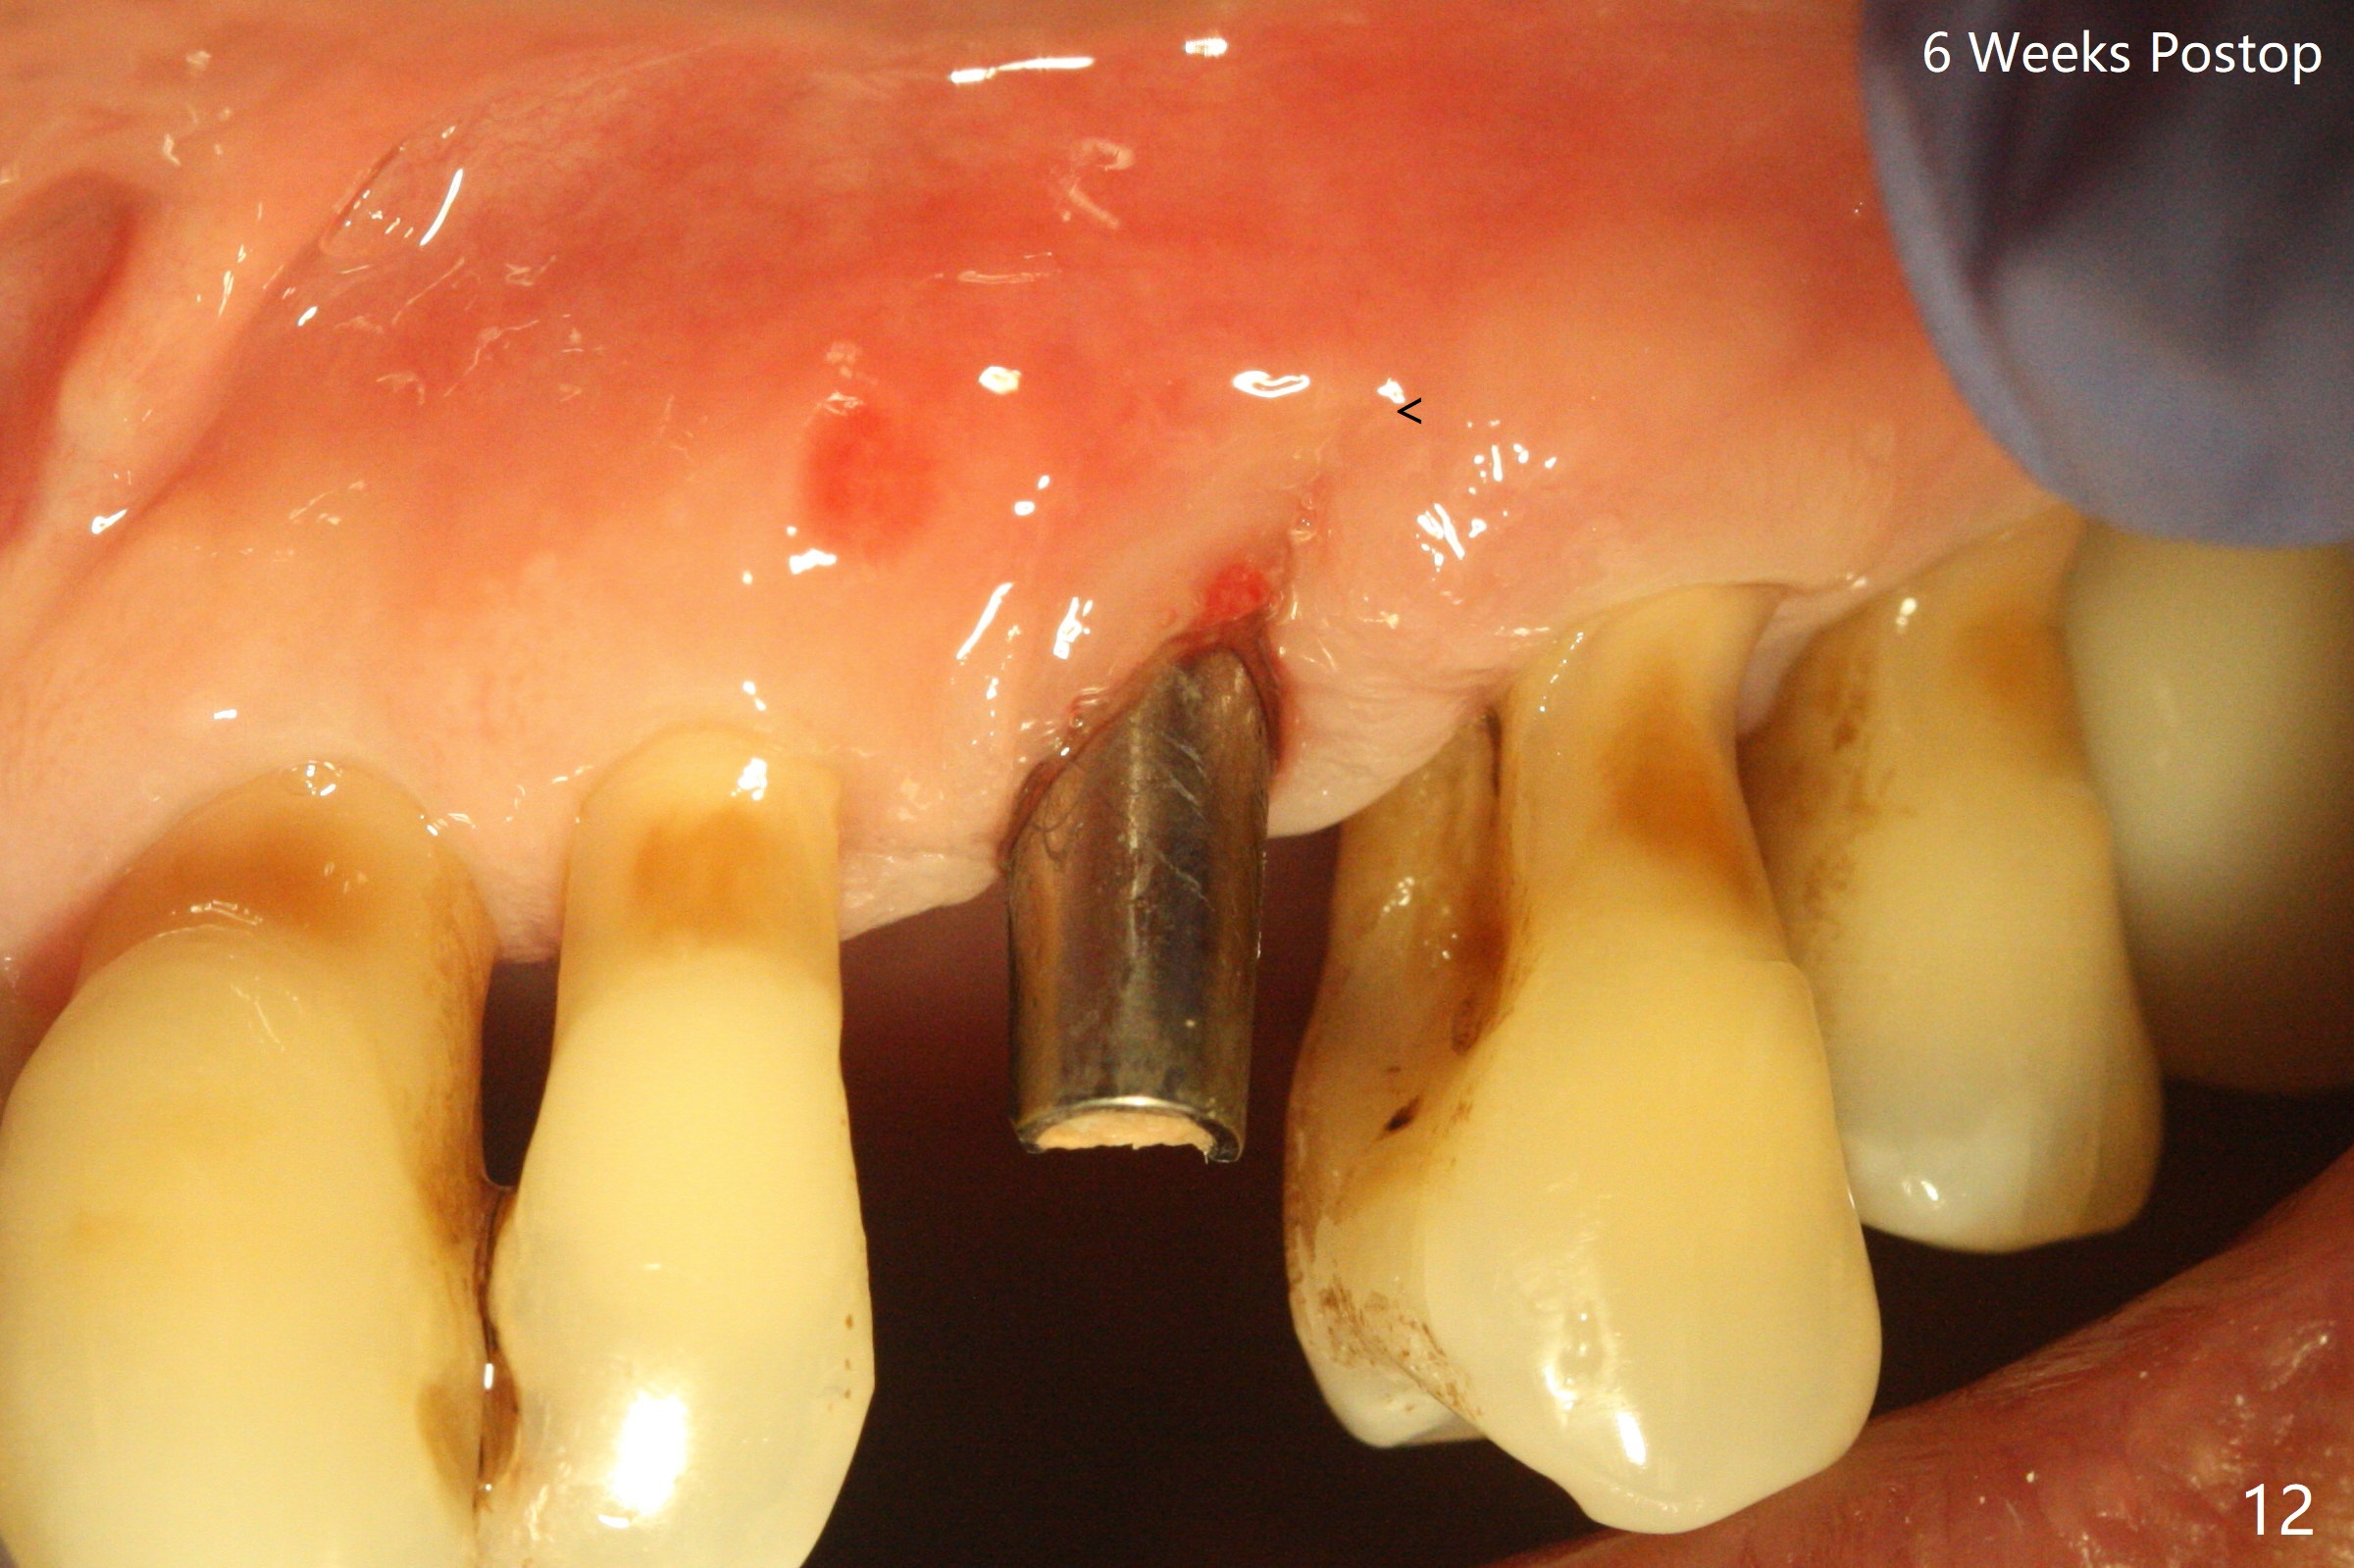

A 62-year-old man with generalized chronic periodontitis returns with chief complaint of loose tooth at #11 (Fig.1). Although a buccal fistula (Fig.1 <) is closer to #12 than to #11, percussion is more severe at #11 than 12. The buccal plate of #11 is missing, but it is possible to place a narrow immediate implant because of the wide alveolus (Fig.2). Since the gingiva is ~ 10 mm long, a mill abutment is to be used (Fig.3,5). In fact the fistula communicates with #11 extraction socket. After debridement, osteotomy is initiated (Fig.4) for a 3.8x10 mm implant ~ 35 Ncm, followed by seating a 4.5x2 mm mill abutment (Fig.5). Abundant sticky bone is placed in the remaining socket (for buccal plate reconstruction) and against the root surface of the neighboring teeth (Fig. 6 * (#10,12)). Finally 2 pieces of PRF membranes are utilized to facilitate repair of the buccal soft tissue defect (Fig.7 *). The root prominence of the canine seems to be maintained by the bone graft (Fig.8 C). Acrylic dressing holding the PRF membranes in place remains in situ with the healthy gingiva buccal (Fig.9) and palatal (Fig.10) 11 days postop. Note the acrylic locking into the undercuts of the neighboring teeth (*). 经过一段摸索发现离心每分钟1500转5分钟后,抽取上清液,接着再离心10分钟剩余上清液就形成血小板块,压制后便是血小板膜,后者似乎有助于软组织愈合,而上清液用来制备骨块,帮助硬组织生长。利用这个原则讨论以下病例治疗。The gingival margin gains ~ 5 mm 6 weeks postop when the acrylic dressing is removed (Fig.11,12 (<: previous one), as compared to Fig.7,8). 治疗结束时尖牙牙龈缘高于第一双尖牙(图七,八),六个星期后,尖牙牙龈缘却低于双尖牙(图十一,十二(箭头:原始牙龈缘))。术后2.5,4.5月基台周围牙龈似乎能与钛合金附着,防止细菌进入深部植体(图十三,十四)。临时牙冠脱落多次,可能与mill abutment太光滑有关,所以颊侧,舌侧磨成平面(图十四)。取模时好像不必取出基台清洗(仿佛没有炎症),原位用树脂延长基台。术后5个月CT显示颊侧骨板再生(图十六-十八)。取模时并没有用树脂加长基台;粘固时,牙冠颜色理想,但是照片中并不是如此(图十九,二十),颊侧骨板没有塌陷。术后11个月基台颊侧骨板没有萎缩(图二十一:B);3d图像:骨壁完全形成(图十六对比:部分形成)。密度也增高(图二十二:B),与术后五个月比较(图十七)。术后十一个月,粘固后五个月角化龈存在(图二十三),牙冠颈部有金属颜色透出,是因为二段式基台太粗了(最细4.5毫米),可以请实验室在牙冠内部涂opaque material而减轻。